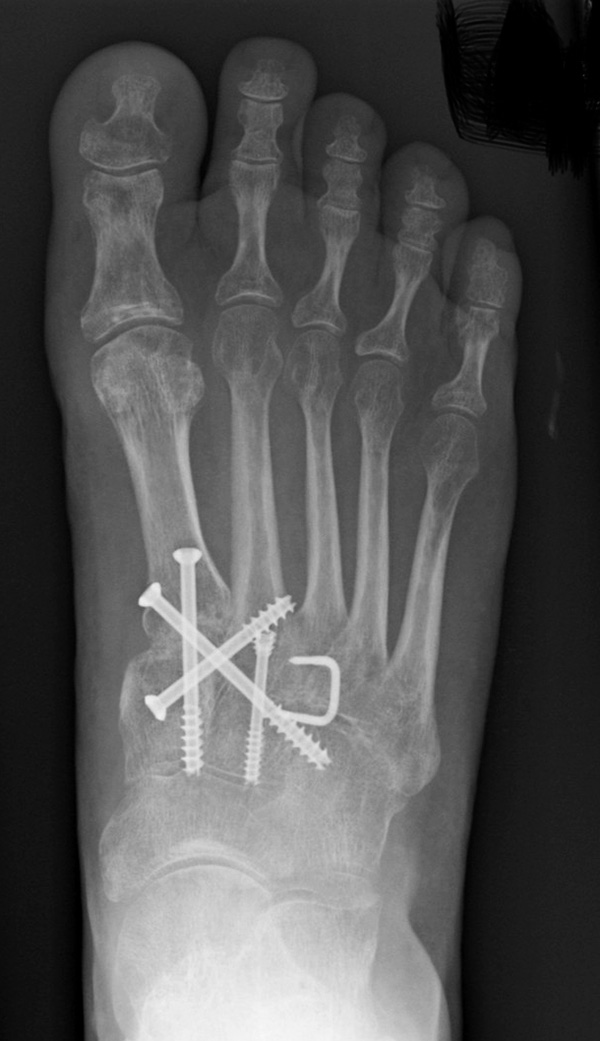

In der Regel werden die physiologisch rigiden TMT-1 bis 3 mittels Schrauben transfixiert. Hierfür werden meist kanülierte Kleinfragment-Kortikalisschrauben (3,5 oder 4 mm) verwendet. Diese können in Stellschraubentechnik von der Metatarsale-1-Basis in das Os cuneiforme mediale (Abb. 17) sowie vom Os cuneifome mediale in die Metatarsale-2-Basis und bei zusätzlicher intercuneiformer Instabilität vom Os cuneifome mediale in das Os cuneifome intermedium eingebracht werden.

Zum Lesen der Bildbeschreibung und zur Vollansicht bitte das Bild anklicken.

Ggf. wird zusätzlich ein K-Draht oder eine Schraube von der Metatarsale-2-Basis in das Os cuneiforme intermedium gebohrt (Abb. 18). Zur Transfixation der TMT-4 und 5-Gelenke werden, entsprechend ihres höheren physiologischen Bewegungsumfangs meist K-Drähte empfohlen. Die Indikation zur Transfixation wird von den meisten Autoren nur bei einer Instabilität gesehen, einige empfehlen eine Transfixation sämtlicher TMT-Gelenke unabhängig vom Ausmaß der Instabilität 10. Kleine, nicht refixierbare Fragmente sollten entfernt werden. Ist ein primärer Hautverschluss nicht möglich, erfolgt die temporäre Weichteildeckung mit Kunsthaut wie Epigard 112951710.